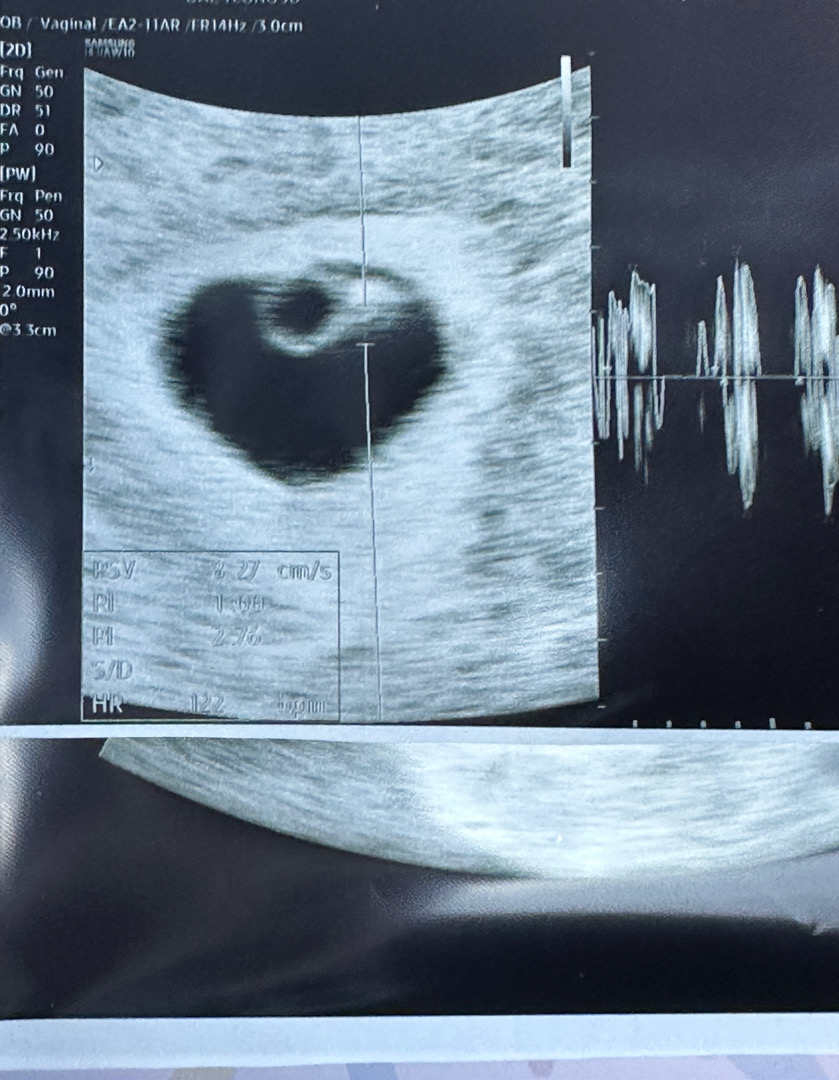

오늘 심장소리 듣고 왔어요>.<6주차

오늘이 두번째 병원 방문이에요 ..! 명절 전에 심장소리 들어야 안심이 될것 같아서 남편이랑 같이 다녀왔는데요 아직 아가 크기가 3mm라는데 심장소리가 엄청 크게 콩닥콩닥 들려서 너무 귀여운거 있죠?ㅋㅋㅋ 기특하기도 하고 기분이 이상하더라구요 사실 아직 초기라 가끔 임신했는지 모를 정도로? 몸에 아무런 변화가 없어서 실감이 안났는데 오늘 심장소리 들으니까 진짜 임신한게 실감 나더라구요 ㅠㅠ 무럭무럭 자라서 건강히 태어났으면 좋겠어요🤍